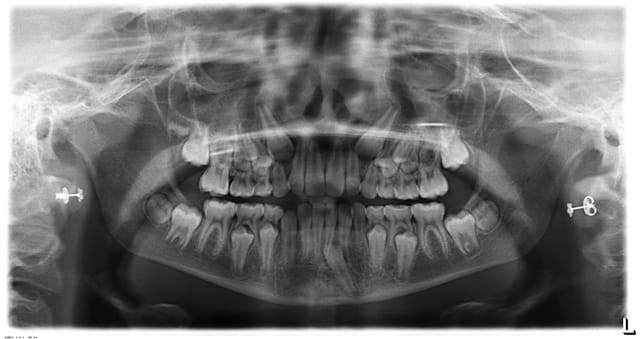

petit cas, commencé il y a quelques années.

C'est de l'ortho mais je suis omnipraticien.

Le cas ou j'ai le plus galéré ( classe 3 et surtout 43 incluse ), mais qui m'apporte beaucoup de satisfaction.

fille d'un ami en plus!